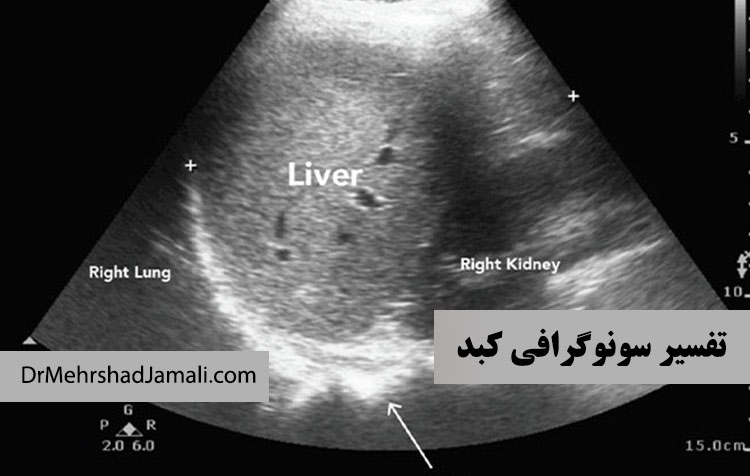

سونوگرافی کبد شما می تواند چیزهای زیادی در مورد آن نشان دهد. یک ارائه دهنده مراقبت های بهداشتی ممکن است سونوگر

کبد چرب چیست؟ علائم، علتها، روشهای درمان، رژیم غذایی مناسب، گریدهای بیماری و بهترین روشهای تشخیص مانند سونوگرافی ک